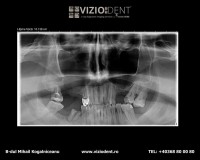

- radiografie panoramică

- radiografie panoramică 1/2

- radiografie panoramică bitewing